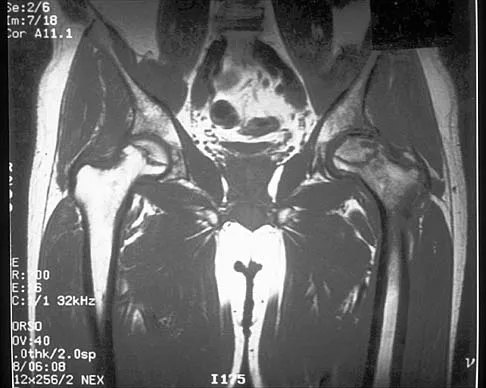

Figures 61a and 61b show the CT and MRI scans of a 40-year-old man who has hip pain. He undergoes total hip arthroplasty and curettage and cementation of the lesion as shown in Figure 61c. Histopathologic photomicrographs of the curettage specimen are shown in Figures 61d and 61e. What is the best course of treatment?

Explanation

The definitive surgery would be removal of the entire resection bed, and in this case of dedifferentiated chondrosarcoma, a hemipelvectomy was performed. The MRI and CT scans show an aggressive cartilage lesion. The histology, representative of a dedifferentiated chondrosarcoma, shows a bimorphic low-grade cartilage lesion with high-grade spindle cell sarcoma. The cartilage lesion is usually an enchondroma or low-grade chondrosarcoma. The dedifferentiated portion is typically a malignant fibrous histocytoma, osteosarcoma, or fibrosarcoma. Weber KL, Pring ME, Sim FH: Treatment and outcome of recurrent pelvic chondrosarcoma. Clin Orthop Relat Res 2002;397:19-28.